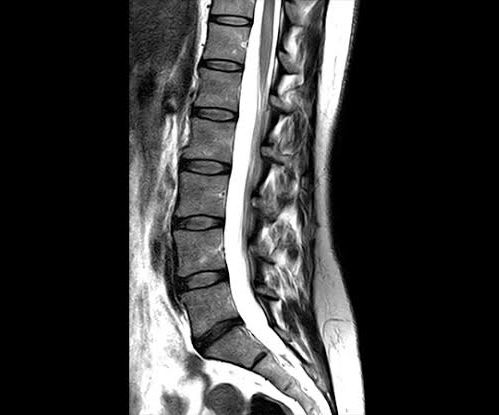

Cirugía de columna vertebral

Fracturas Vertebrales

Espondilolistesis

Hernias de Disco